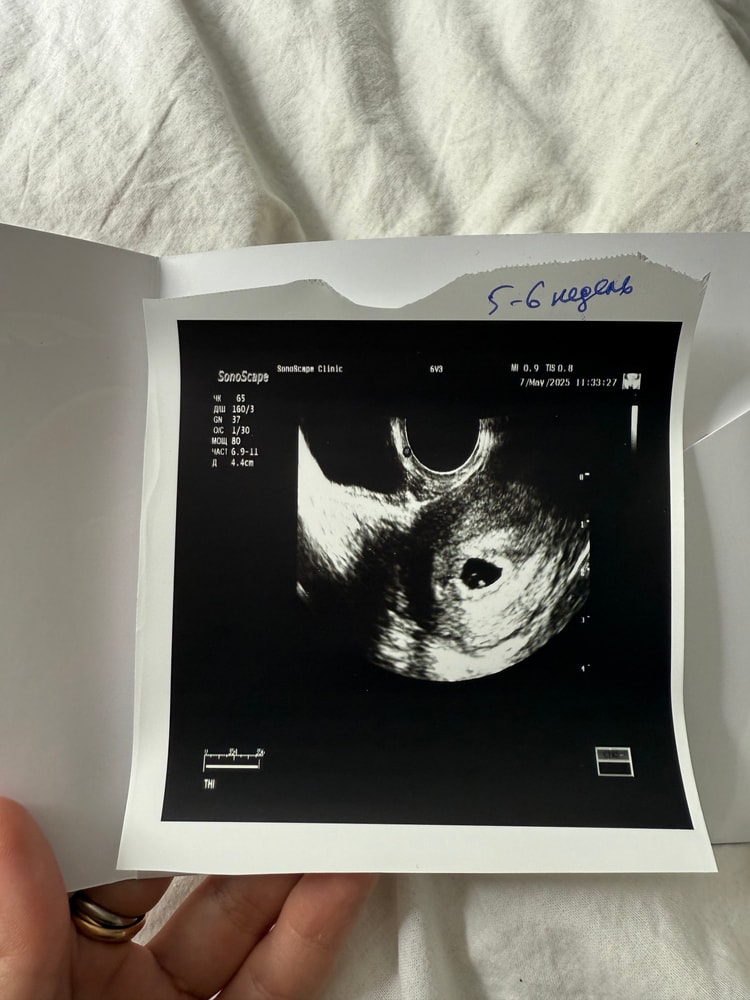

УЗИ 20дпп

Срок: 5 недель 4 дня

Диаметр пя 8,3, жм 2,9мм

В заключении написали, что эмбрион пока не визуализируется, но его зачатки уже видно, а еще была видна пульсация похожая на сб, но ре сказала, что возможно сосуд пульсирует

А еще небольшая гематома 6,5мм, сказали не страшно, часто бывает при переносе эмбриона